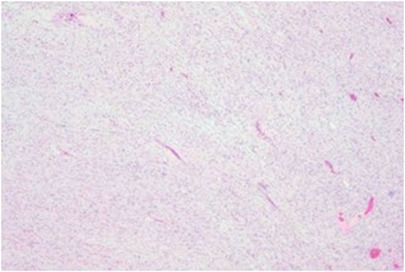

Background: Ganglioneuroma (GN) of the lumbar spine is rare, typically occurring in children and young adults. Its diagnosis in middle-aged patients can be challenging. This paper reports a case of a dumbbell-shaped lumbar GN in a middle-aged woman. Case: A 46-year-old woman presented with low back pain and radiating leg pain. MRI revealed a dumbbell-shaped mass at the L2 level. She underwent posterior microscopic total tumor resection with L2-L3 pedicle screw fixation. Postoperative pathology confirmed GN. Conclusion: At the 1-year follow-up, there was no recurrence. For dumbbell-shaped lumbar GN, a posterior approach combined with internal fixation is an effective strategy. This case suggests that GN should be considered in the differential diagnosis of foraminal masses in middle-aged patients.